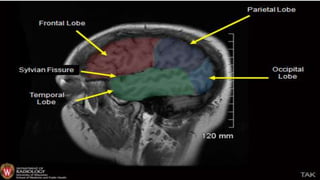

LOBES

FUNCTIONS OF LOBES

Eloquent areas

A. Eloquent cortex is a name used by neurologists for

areas of cortex that—if removed—will result in loss

of sensory processing or linguistic ability, or paralysis.

B. The most common areas of eloquent cortex are in the

A. Left temporal and

B. Frontal lobes for speech and language,

C. Bilateral occipital lobes for vision,

D. Bilateral parietal lobes for sensation, and

E. Bilateral motor cortex for movement